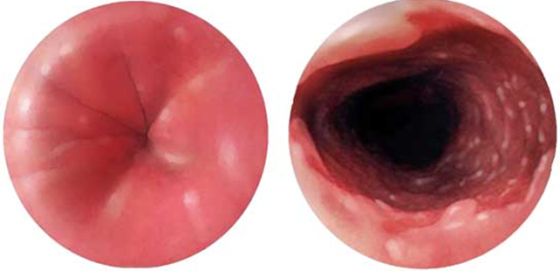

Diaqnozun dəiqiləşdirilməsi üçün kontrastlı Rentgenoloji müayinələr, KT və çox ehtiyatla endoskopiya edilir.

- Kontrastlı Rh-qrafiya - diaqnozu dəqiqləşdirən müayinədir.

- Endoskopiya - divertikulun perforasiyası təhlükəsinə görə çox ehtiyatla aparılmalıdır.

Endoskopik stapler

Divertikul ilə QB arasındakı arakəsmə endoskopik staplerlə kəsilir və tikilir. 3-6 sm ölçülü divertikullarda icra edilir.